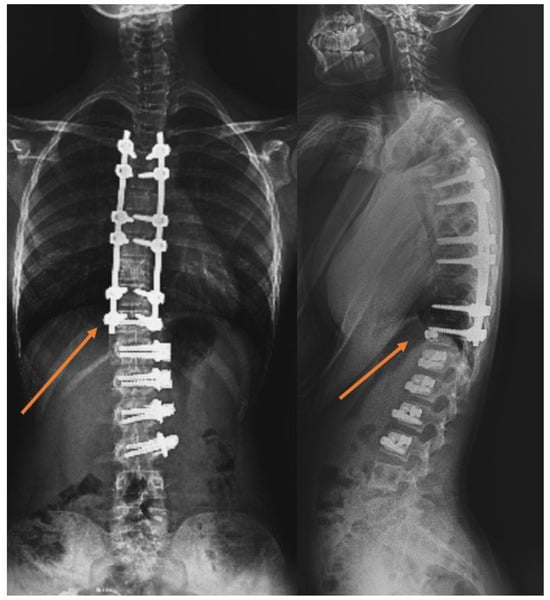

Background/Objective: The anterior vertebral body tethering (AVBT) technique, which preserves spinal mobility and avoids possible fusion problems in adolescent idiopathic scoliosis (AIS) patients, continues to be increasingly used in spine surgery. The study aims to report the early-to-early-mid postoperative radiological results of thoracolumbar/lumbar AVBT on sagittal alignment, and the second aim is to compare AVBT with selective thoracic fusion (STF) and non-selective fusion (NSF) groups in AIS patients. Methods: Patients with a diagnosis of AIS were retrospectively evaluated in the study. All patients were categorized into three groups based on the surgical technique performed: AVBT (n = 17), NSF (n = 19), and STF (n = 15). The major curvature degree, coracoid height difference (CHD), sacral slope (SS), pelvic tilt (PT), pelvic incidence (PI), lumbar lordosis (LL), thoracic kyphosis (TK), cervical lordosis (CL), C7 tilt, sagittal vertical axis (SVA), T1 pelvic angle (TPA), and T1 spinopelvic inclination (T1SPI) were measured for radiological comparison. Scoliosis Research Society-22 (SRS-22) and Oswestry Disability Index (ODI) scores were used at the final follow-up for functional evaluation. Results: The T1SPI value of the NSF group was significantly higher than the STF group in the final follow-up (p = 0.033). The mean decrease of 8.85 ± 7.85 units in the final follow-up value compared to the postoperative CHD value of the patients in the AVBT group was found to be significant (p = 0.028). Statistically significant differences were found between preoperative and the first postoperative CL and TPA measurements (p = 0.001 and p = 0.042, respectively), as well as between preoperative and final follow-up CL measurements in the AVBT group (p = 0.001). No statistically significant differences were observed between the groups in CHD, SS, PT, PI, LL, TK, CL, C7 tilt, SVA, and TPA values (p > 0.05); similarly, the SRS-22 and ODI scores did not differ significantly among the groups (p > 0.05). Conclusions: Thoracolumbar/lumbar AVBT surgery led to significant improvements in shoulder asymmetry and cervical lordosis of AIS patients in the early to early-mid postoperative period. However, compared with spinal fusion techniques, thoracolumbar/lumbar AVBT did not demonstrate superiority in functional scores or sagittal parameters. The mid- to long-term benefits of thoracolumbar/lumbar AVBT remain uncertain and require further investigation. Full article

Figure 1